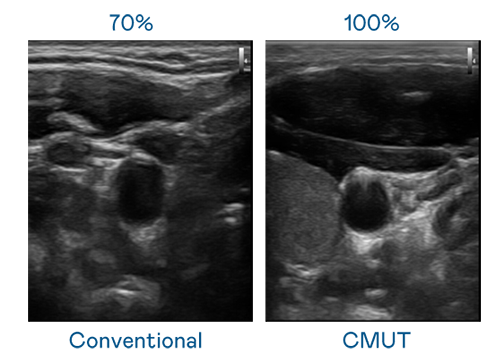

CMUT 技術是一種用電容式微機電元件來產生超音波訊號的技術。與傳統 PZT 壓電式技術相比,CMUT 頻寬增加 30%,更寬頻的超音波訊號讓影像解析度大幅提升,是實現高影像品質醫療超音波掃描、促進精準醫療發展的關鍵技術。

超音波影像的解析度高低,首先取決於探頭能發出的訊號頻寬。long8-龙8(龙八国际)唯一官方网站 CMUT 可提供高清晰的超音波訊號,提供高頻寬、高靈敏度、影像紋理細節更高的超音波影像,協助醫護人員縮短影像判讀時間及利用精準的醫療影像進行診斷。